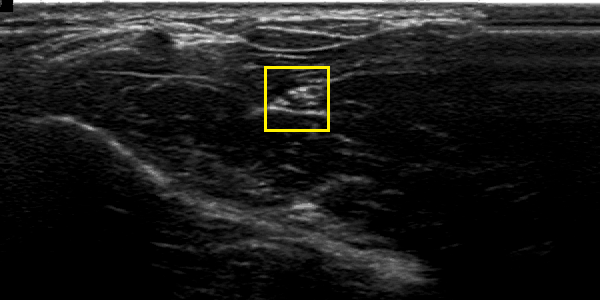

Figure 2 illustrates and example of results in two US images from two different patients. Figures 2 (b) and (e) shows the localisation obtained with CNN and spatiotemporal consistency. The nerve segmentation by PGVF is depicted in figures 2 (c) and (f). One can observe that the automatic segmentation is very close to the one obtained form human experts figures 2 (a) and (d).

Fig. 2: An example of the obtained using deep learning with spatio temporal consistency. Images show the median nerve of two different patients. Left column (a) and (d), each image is the ground truth of the median nerve of each patient. The middle column (b) and (e), represents the localisation result using CNN and spatiotemporal constraint. Right column (c) and (f), shows the segmentation result using PGVF algorithm